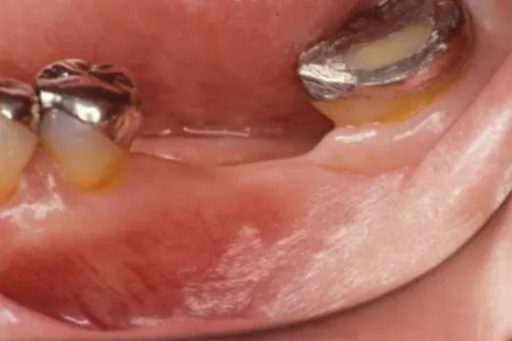

下顎臼歯部が欠損した患者さんのインプラント治療の症例②(うえだ歯科)

| 主訴 | 全顎治療希望、下の奥の歯が無いので全く噛めない。綺麗で噛めるようになりたい |

| 治療内容 | 下顎臼歯部欠損放置のため、臼歯部においてスペースがないため、全顎治療を行い咬合再構成を行う。 早期においてインプラント治療、咬合関係を模索した後、全顎にわたりセラミックによる補綴治療、その後メインテナンスに移行 |

| 治療費 | 5,410,000円(税込)(インプラントすべて含む) |

| 治療期間 | 1年8ヶ月 |

| 治療回数 | 80回 |

| 想定されたリスク | 食いしばり(パラファンクション)によるセラミックの破折、歯の破折 |